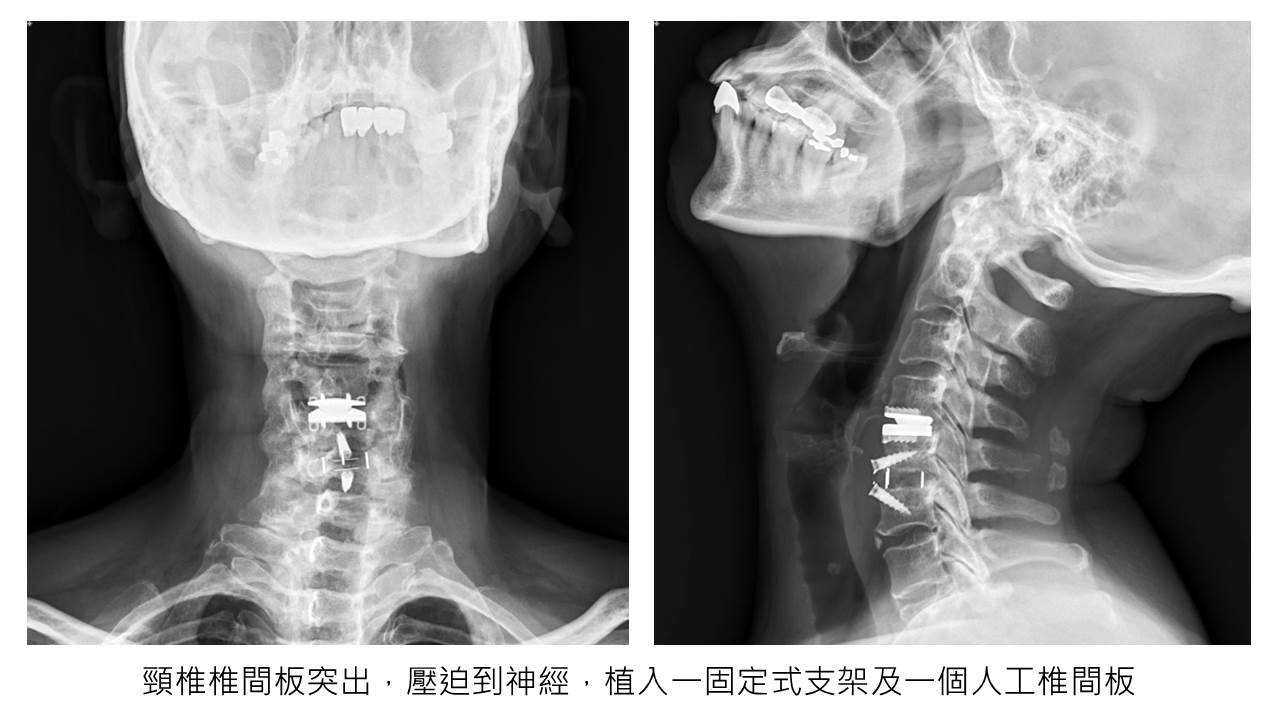

經過X光檢查,發現第五、六頸椎椎間板有退化的現象,於是先安排復健拉脖子,並給予強效止痛藥物,經過兩週保守治療後,症狀未見好轉,因此進一步以磁振造影掃描,顯示第四、五、六頸椎椎間板突出、退化,有明顯神經壓迫。經過與病人詳細解釋及溝通後,病人接受了手術。我們採取前開第四、五、六椎間板切處,並分別植入一固定式支架及一個人工椎間板(見下圖),整個手術時間約一個半小時,出血量小於5 cc。術後四小時,病人即可下床、進食,無須導尿管留置;並於次日早上換藥後出院。術後使用軟式頸圈保護六週,術後當天下午,病人自覺疼痛已改善近八成,惟手指仍有些許麻木,兩週後症狀幾乎完全消失,並可回去市場,從事較輕鬆的工作。